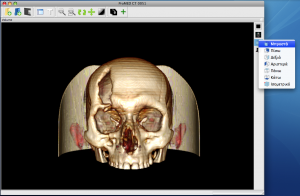

InVesalius is an image processing software dedicated to DICOM images (“.dcm” / “.DCM” extension) produced by imaging equipment (CT, MRI). It is fully compliant with the DICOM standard for image communication and image file formats. InVesalius is able to read 2D images and build 3D models of the region of interest.

InVesalius has been designed for navigation and visualization of multidimensional images: 2D viewer and 3D viewer and also for rapid prototyping anatomical structures. The 3D Viewer offers all modern rendering modes: Multipla

nar reconstruction (MPR), Surface Rendering, Volume Rendering and Maximum Intensity Projection (MIP). Surfaces created by InVesalius can be exported to OBJ, STL or other 3D files supported by Blender or other software. It is completely written in Python. Also, we only use free software tools in its development, including VTK (Visualization Toolkit), wxPython, GDCM (Grassroots DICOM), ITK (Insight Toolkit), NumPy, PIL (Python Imaging Library).